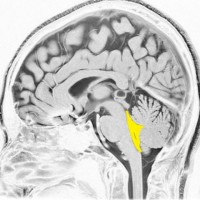

第4脳室とは

後頭部に近い所にあります。黄色が第4脳室で,髄液の通り道(出口)です。

前方には脳幹部,後ろは小脳虫部です 。

上は細い中脳水道につながって,下はマジャンディー孔と左右のルシュカ孔に開いています。